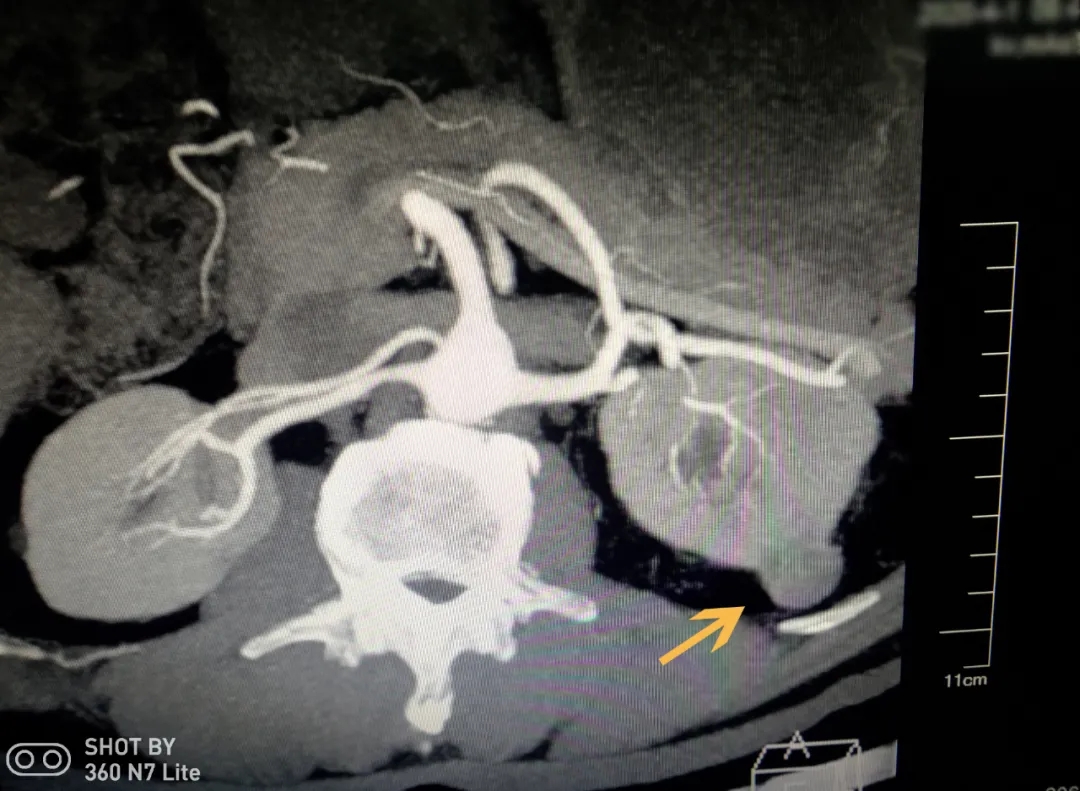

CT检查显示患者左肾有肿瘤

3月下旬,62岁的黎先生发现自己反复胀痛一年多的腰部越来越难以忍受,赶忙来到我院就医。泌尿外科医生检查发现黎先生左肾中上级背侧有一块直径约2cm的肿瘤,建议采取手术切除以免肿瘤继续生长。